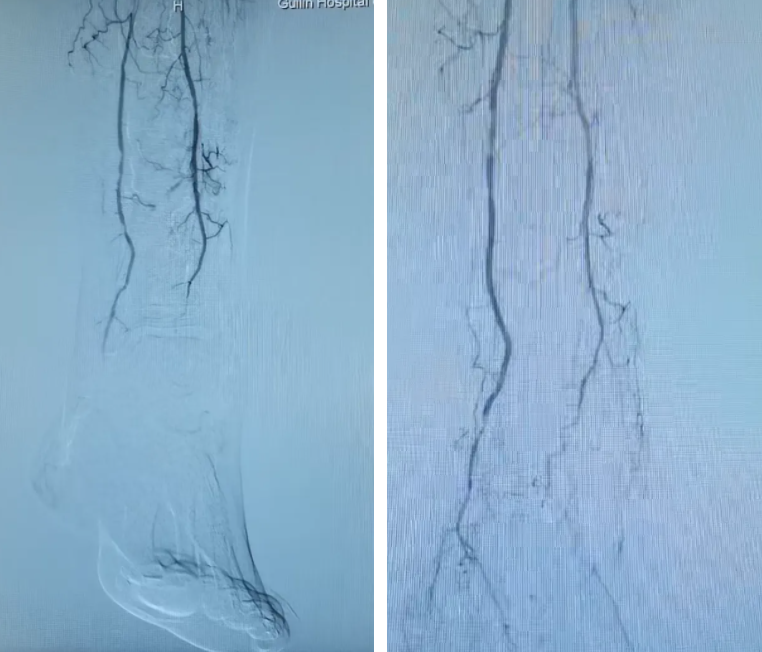

IVUS引导下的准分子激光斑块消蚀术中影像

足部动脉的术前(左)术后(右)影像对比